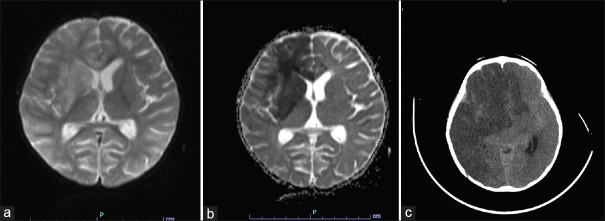

Results: 204 /416 children with suspected meningoencephalitis were included in the study. HHV 6 was detected in 12 children. The median age was 19 months (Range - 6 months to 16 years). 4 (33%) of them were classified as febrile status. 5 (42%) children had meningoencephalitis, and one had aseptic meningitis. One child each had features of probable acute demyelinating encephalo myelitis (ADEM) and anti NMDA receptor encephalitis. 9 (75%) children had uneventful clinical recovery, one child died, one child with probable ADEM had extrapyramidal signs at discharge, which improved completely at one year follow up and the baby with autoimmune encephalitis had significant neurological deficits.